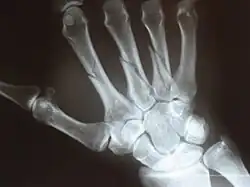

Left hand shown with thumb on left.

The metacarpals form a transverse arch to which the rigid row of distal carpal bones are fixed. The peripheral metacarpals (those of the thumb and little finger) form the sides of the cup of the palmar gutter and as they are brought together they deepen this concavity. The index metacarpal is the most firmly fixed, while the thumb metacarpal articulates with the trapezium and acts independently from the others. The middle metacarpals are tightly united to the carpus by intrinsic interlocking bone elements at their bases. The ring metacarpal is somewhat more mobile while the fifth metacarpal is semi-independent.[1]

Each metacarpal bone consists of a body or shaft, and two extremities; the head at the distal or digital end (near the fingers), and the base at the proximal or carpal end (close to the wrist).